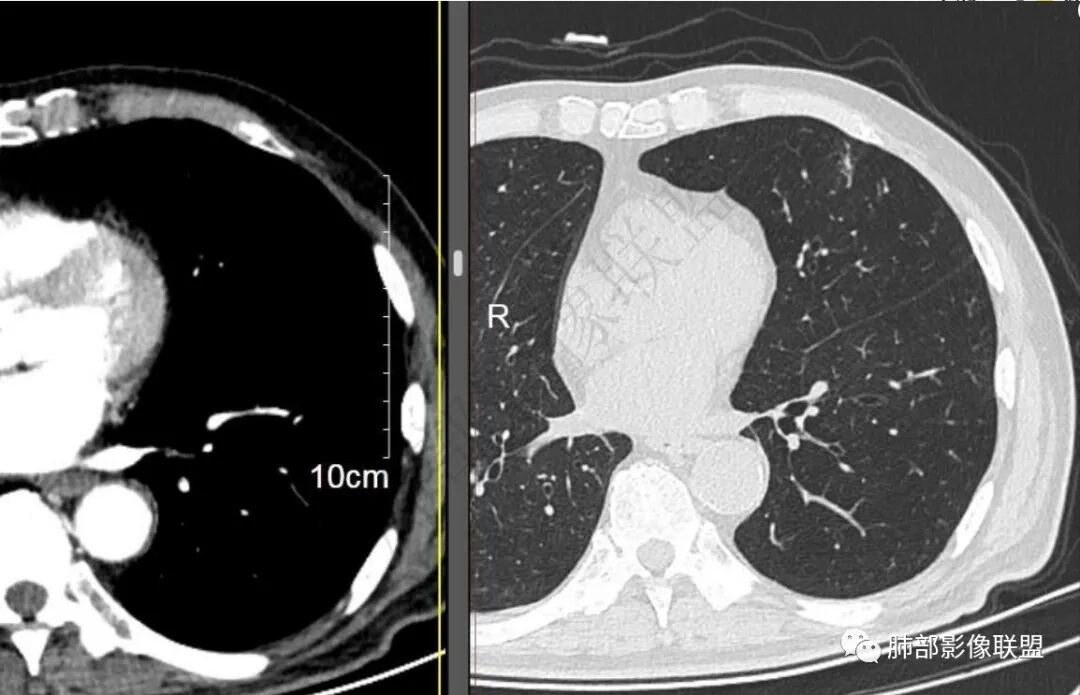

9个月后病灶明显增大,边缘较平直,部分膨隆,锁扣样外观,仍旧缺乏典型深分叶及张力,未见胸膜凹陷。

再1个多月后病灶继续增大,较明显不均匀强化,肺门一侧见低密度区。病灶边缘相对不清,可见毛刺。